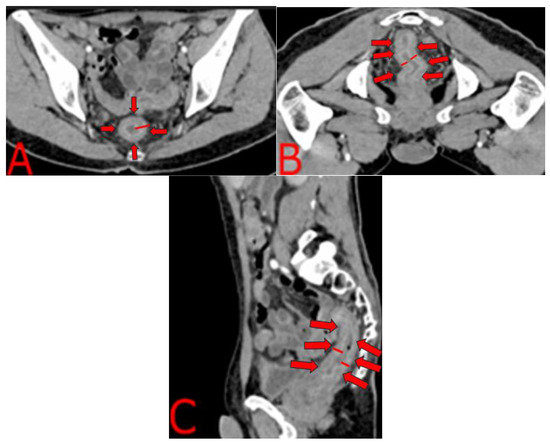

2.4. Imaging and Endoscopic Findings

| This work (2025) | Wt loss, ↑diarrhea, hematemesis, fever, pain | ERG+ capillaries; CD38+ plasma cells | CT “target sign”; colonoscopy: exudates, ulcers | Trep-EIA+; VDRL 1:64 | PCN G IM × 3 wk + TMP/SMX and AZM + Dox + ART |